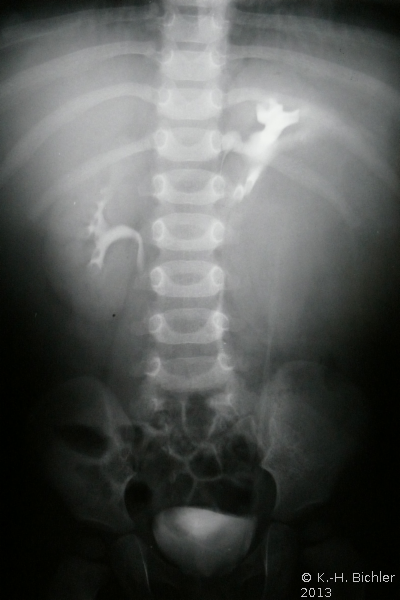

Die abdominale Sonographie bzw. die Computertomographie haben die Ausscheidungsurographie als die bildgebende Untersuchungstechnik bei Patienten mit Oberbauchtumor, z.B. Wilmstumor, verdrängt. Einige Ausscheidungsurographien von Kindern mit Wilmstumoren aus unserer Sammlung aus den 70er Jahren des vergangenen Jahrhunderts sind aus didaktischen Gründen hier wiedergegeben. Die Bilder zeigen instruktiv die Größe und Verdrängung durch den Tumor (

4 Abbildungen HG1).